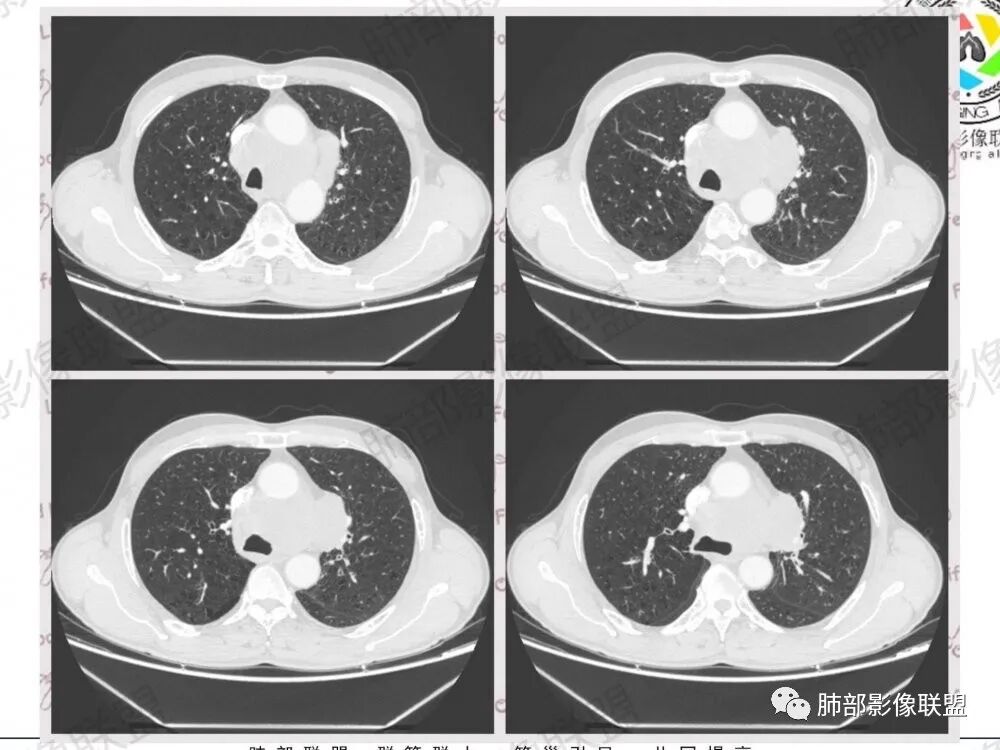

影像特点:

1.左肺门及纵隔见异常增大淋巴结,部分融合,不均匀轻度强化,未见明显坏死。

肿大淋巴结与纵隔血管等结构“无缝”贴合。

2.纵隔增宽但依旧居中。

1.这应当是常见的小细胞肺癌的转移方式。

别忘了,患者左肺上叶那个略显饱满的的小结节,有理由相信那是发源地。

因为这些符合肺癌的整个转移路径!